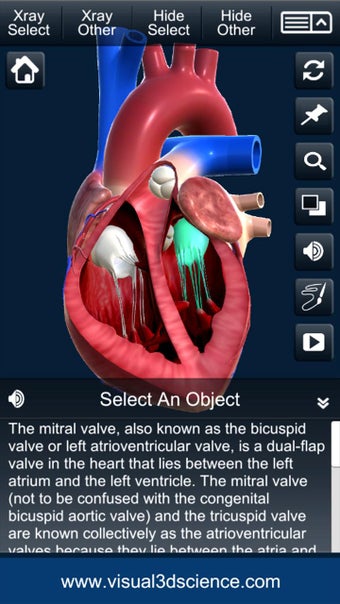

El usuario puede seleccionar cualquier parte del corazón para ver su nombre o leer información relacionada.

Puedes seleccionar la vista de rayos X, ocultar y mostrar partes del corazón, así como ver animaciones en tiempo real, dibujar o escribir en la pantalla y compartir capturas de pantalla, pronunciación de audio para todos los términos de anatomía y más.